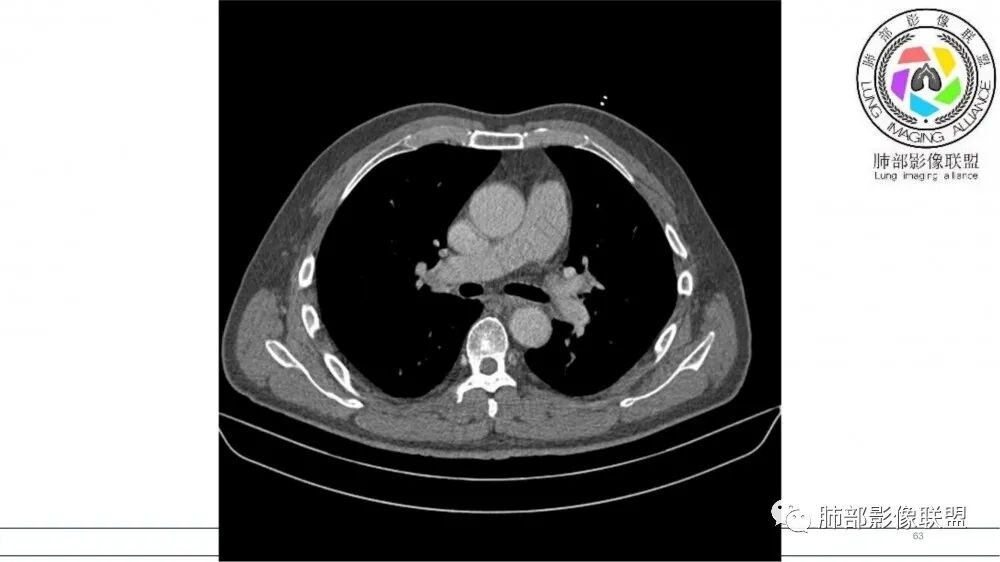

左肺上叶前段支气管内铸形生长软组织影,增强后均匀强化,远侧见斑片状磨玻璃影。考虑恶性病变,粘表?粘液腺?

老年男性,左肺上叶前段支气管内铸形阴影,增强后病灶不均匀强化,内部有坏死?远端可见斑片状阴影(阻塞性肺炎)。考虑恶性病变,老年人,鳞?类癌?粘表不能排除。

左肺上叶前段支气管杵状指样扩张,内见实性组织阻塞性,并强化明显,边缘饱满,周边多发小斑点影,小花小草征,老年男性,长期吸烟史,方向恶性,首选支气管内浸润鳞Ca可能性大。

老年男性,肺气肿,吸烟史,左肺上支气管腔内铸型高密度影,呈指套状,远端多发树芽,增强不均匀强化,考虑鳞癌,鉴别小细胞癌

B3指套征,常规不是鳞癌就是ABPA,有强化丶血管造影征,倾向于鳞癌

进一步查支气管镜,有胸闷,看看嗜酸性粒细胞高不高,查一下曲霉菌特异性ⅠgG丶ⅠgE,总lgE鉴别ABPA

病灶沿支气管生长,强化不均匀,坏死不明显,血管自然进入,支持恶性,小在先,鉴别淋巴瘤

老年男性,吸烟史,左肺上叶支气管塑形生长肿块,整体边缘较圆钝,不均匀强化,血管走形,形态较纤细,病灶远端可见花草样改变,恶性,先考虑小细胞癌鉴别鳞癌

老年男性,长期吸烟史。左上肺前段沿支气管走形的指套样病变,增强可见病灶强化(排除结核、ABPA(也无气喘症状)),远端多发点状高密度影。考虑恶性肿瘤,鳞癌可能性大。

指套征,扩张支气管内软组织强化,远侧肺野阻塞性炎,纵隔、左肺门肿大淋巴结;老年男性,吸烟,考虑鳞癌,鉴别小

老年男性,术前检查肺气肿背景,左肺上叶结节,沿支气管蠕虫样生长,左肺门及纵隔淋巴结肿大,增强扫描不均匀强化,血管包绕,结合吸烟史,考虑小细胞肺癌。

老年男性,吸烟,指套征,蠕虫征,阻塞性炎症不严重。可见血管穿行,密度均匀,轻度强化,首先考虑小细胞肺癌。鉴别鳞

2021年8月6日晨读病例结果:小细胞肺癌

指套征:是影像征象,胸部平片表现为手指状密度增高影,以肺门为中心呈放射状分布,CT显示扩张支气管内低密度黏液栓形成或实性病变,呈管状、树枝状或卵圆形密度增高影;支气管扩张伴近端梗阻时,扩张支气管内部黏液分泌物不能排出而形成。可以伴随远端空气潴留征、阻塞性炎症。

研究报道,中心型 SCLC 经 CT 扫描后通常支气管表现为鼠尾样狭窄,肺门或纵隔肿块明显,由于肿块沿管壁生长表现为顺延支气管形态的不规则形状。病灶相对特征性影像学表现比如鸭蹼状、腊肠状、葫芦状及葡萄状改变,可以出现血管包埋,很少有空洞、空泡,较少引发肺不张,阻塞性炎症成都较轻。与一般肺癌比较,恶性程度高,侵袭力强、病灶很小就容易远处转移!Herzberg 等[19]研究指出,20%以上 SCLC 倍增时间短,预后不良。